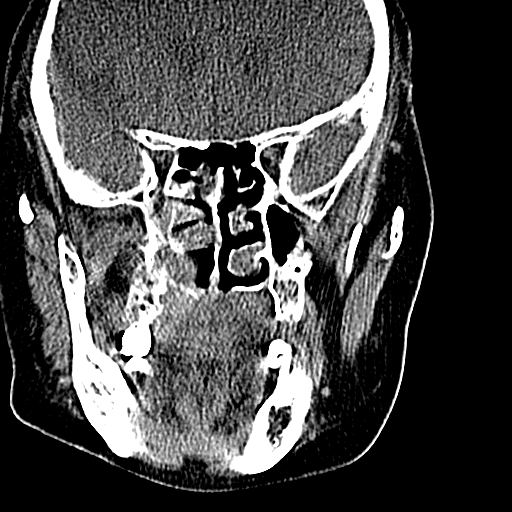

标题: CT19708:单侧上颌窦病变

老年患者,女。鼻塞多年。

考虑右侧上颌窦良性占位性病变,粘液囊肿可能性大;建议活检。

膨胀性生长,且骨质无破坏,说明时间久,良性;从密度,边缘看,内部还见坏死区,应该是实性肿瘤,定性,影像学无绝对的特异性

病灶密度很不均匀,骨壁膨胀中有断裂,考虑内翻乳头状瘤可能性大,粘液囊肿不排除

膨胀性生长,且骨质无破坏,说明时间久,良性;从密度,边缘看,内部还见坏死区,应该是实性肿瘤,定性,影像学无绝对的特异性,考虑内翻性乳头状瘤可能